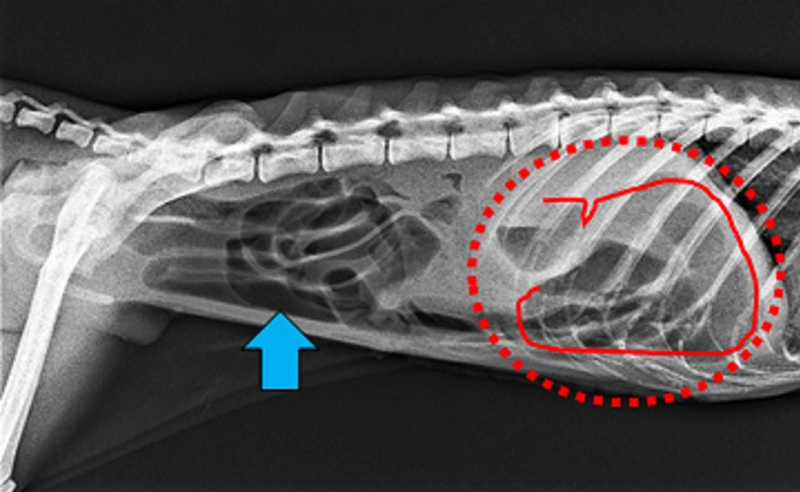

手術前のレントゲン画像

腸管内(青矢印)にガス(黒い領域)が貯留。胃(赤丸)が拡張し、ガスが貯留している